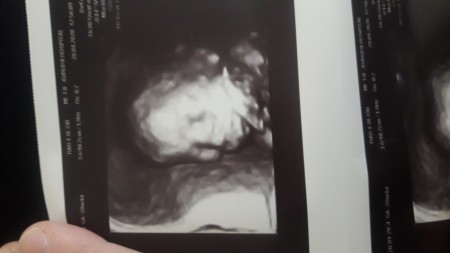

ultrason fotoğrafı çok net çıkmış çok mutlu oldum :) sadece kalbi yavaş atıyo dedi sonra dinledi tekrar tamam şimdi normale döndü dedi içime bi kuşku düştü ama inşallah önemli bişey değildir.

Gebelik haftası 20+5

Ben detaylı ultrasona girmedim canm bu normal ultrason

Oylemi ne kadar net cıkmıs masallah.

Diimi :) ben de çok şaşırdım ❤️